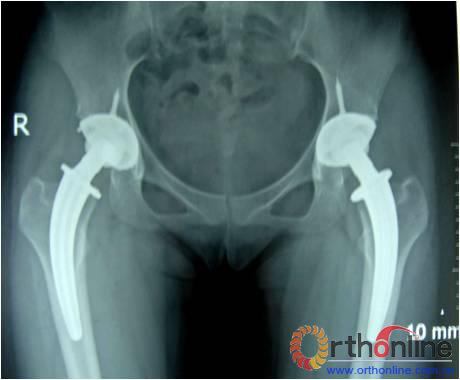

图为:方某,女,21岁,双侧激素性股骨头坏死,ARCO III-C期,C.F.P. 股骨假体THA前后双髋X线摄片。

图1、图2:术前;图3:术后;图4:术后3个月;图5:术后6个月;图6:术后1.2年